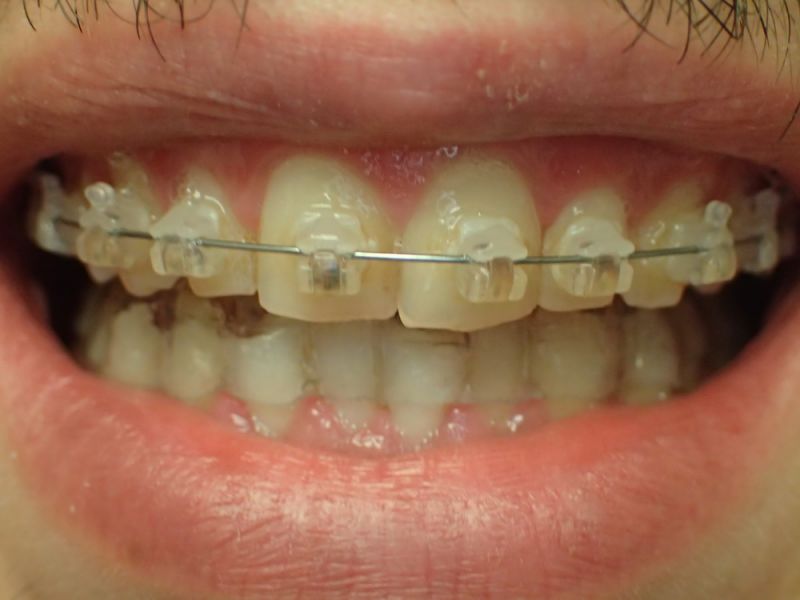

Daraufhin hat der Patient eine Kieferorthopädin konsultiert, die sich nach eigener Einschäötzung auf das Thema CMD spezialisiert hat. Ohne Vordiagnostik hat daraufhin eine Kieferorthopädische Erwachsenenbehandlung begonnen, die mit einer Bebänderung des Oberkiefers begann und nach kurzer Zeit zu geradezu explosionsartig verstärkten Bescherden des Patienten führte. Darauf angesprochen erklärte die konsultierte Kieferorthopädin, nach inzwischen 6000,-€ Behandlungskosten sie wisse nicht mehr weiter und könne dem Patienten nicht helfen.

Es erfolgt dieErstuntersuchung und die Herstellung und Eingliederung eines adjustierten Aufbissbehelfs zum Nachweis einer CMD.